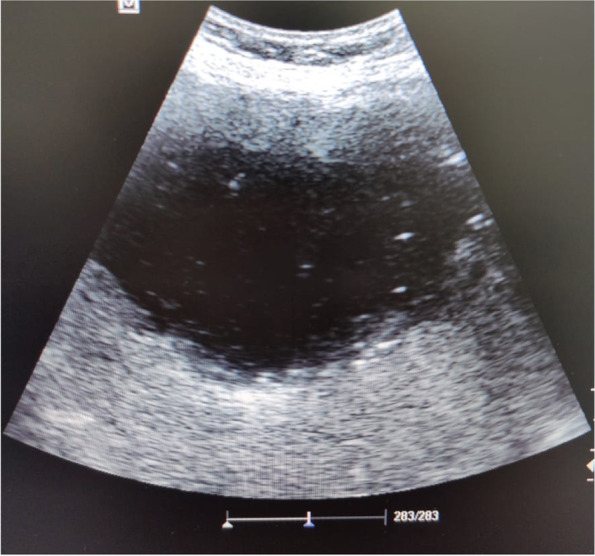

Also, immediate point of care ultrasound (POCUS) revealed a right hepatic lobe focal lesion measuring (10×10cm), along with an evident stent inside the common bile duct (CBD) (Fig. 1). A consecutive computerized tomography scan of the abdomen confirmed the right lobe focal lesion as a complex abscess occupying large area (Figs. 2 and 3).